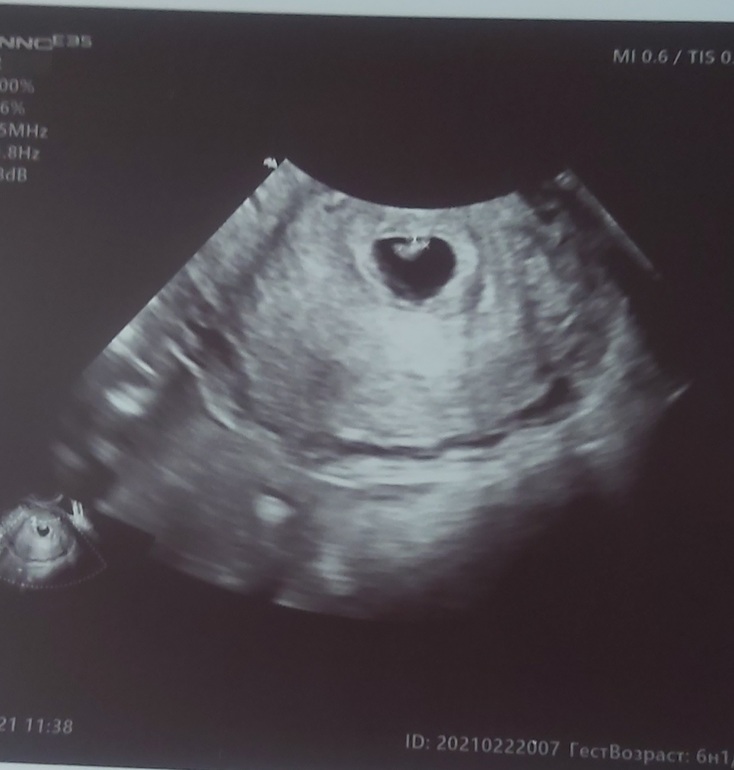

Первое УЗИ😍

УЗИ, КТГ, доплерЕле дотерпела и сходила наконец-то на УЗИ. Срок по месячным и по Узи совпадает. 6.1 👌 сердечко стучит)) малыш 4 мм. токсикоз накрыл конкретно. Тошнит в режиме нон-стоп.

А теперь вопрос, что там с полом по методу Рамзи? Кто разбирается подскажите. Узи трансвагинально делали.